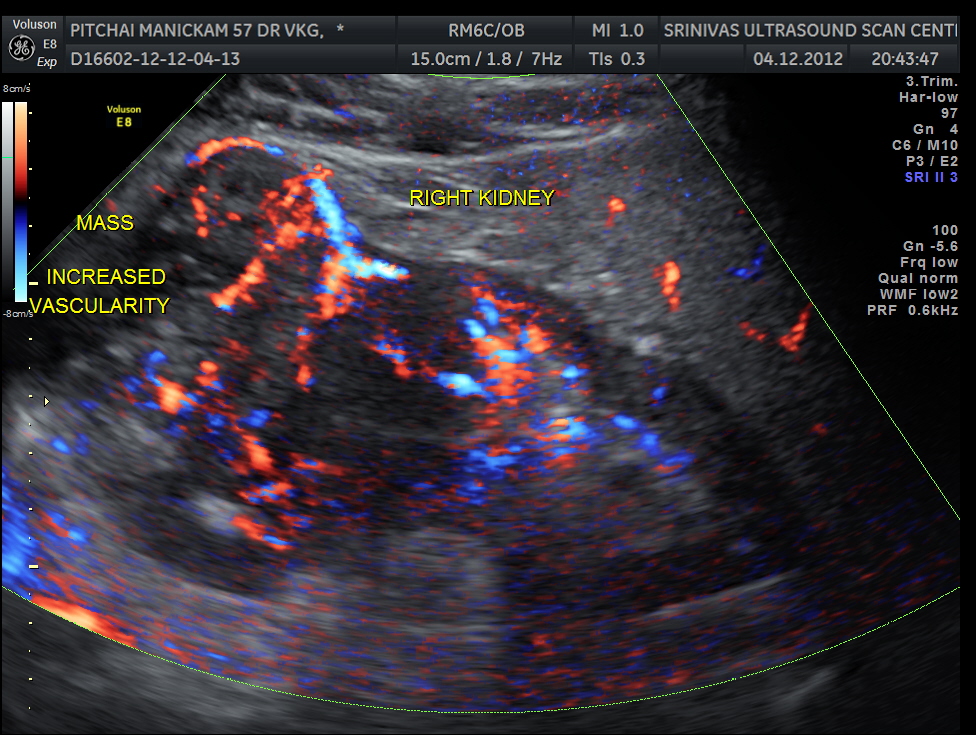

The right renal mass shows increased vascularity .

The images are presented to show the increased vascularity on colour Doppler and the lobularity seen in the reconstructed image and also for the clinical presentation of pain on the contralateral side due to herpes zoster.